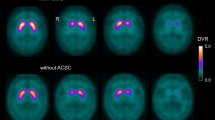

To design a novel algorithm (BasGan) for automatic segmentation of striatal 123I-FP-CIT SPECT.

The BasGan algorithm is based on a high-definition, three-dimensional (3D) striatal template, derived from Talairach’s atlas. A blurred template, obtained by convolving the former with a 3D Gaussian kernel (FWHM = 10 mm), approximates striatal activity distribution. The algorithm performs translations and scale transformation on the bicommissural aligned image to set the striatal templates with standard size in an appropriate initial position. An optimization protocol automatically performs fine adjustments in the positioning of blurred templates to best match the radioactive counts, and locates an occipital ROI for background evaluation. Partial volume effect correction is included in the process of uptake computation of caudate, putamen and background. Experimental validation was carried out by means of six acquisitions of an anthropomorphic striatal phantom. The BasGan software was applied to a first set of patients with Parkinson’s disease (PD) versus patients affected by essential tremor.

A highly significant correlation was achieved between true binding potential and measured 123I activity from the phantom. 123I-FP-CIT uptake was significantly lower in all basal ganglia in the PD group versus controls with both BasGan and a conventional ROI method used for comparison, but particularly with the former. Correlations with the motor UPDRS score were far more significant with the BasGan.

The novel BasGan algorithm automatically performs the 3D segmentation of striata. Because co-registered MRI is not needed, it can be used by all nuclear medicine departments, since it is freely available on the Web.